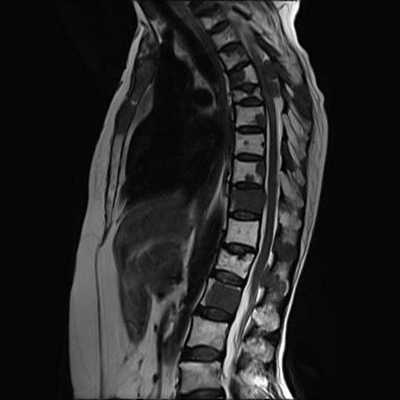

Гемангиомы на магнитно-резонансной томографии грудного отдела позвоночника (сагиттальная проекция, Т2 взвешенная последовательность)

МРТ позвоночника - высокоинформативный метод диагностики, использующий для построения детальных изображений структур области интереса свойства магнитного поля, радиоволны и компьютерную обработку. По показаниям исследование выполняют с контрастным усилением: в вену вводят препарат, содержащий хелаты гадолиния.

МРТ грудного отдела позвоночника (сагиттальная проекция, Т1 ВИ)

Магнитно-резонансные томограммы отображают внутренние структуры зоны интереса в трех плоскостях. Каждый снимок представляет собой один срез, на распечатанном фото МРТ их несколько.

В норме позвонки гладкие, повреждения отсутствуют. Фиброзно-хрящевые диски, выполняющие роль амортизаторов, не выпячиваются, имеют стандартную высоту, без признаков дегенерации. Спинной мозг выглядит на фото как белый шнур без видимых перекосов и других изменений.

МРТ позвоночного столба: грыжа диска L4-L5 (сагиттальная плоскость, Т2 ВИ)

При патологических процессах снимки могут демонстрировать: